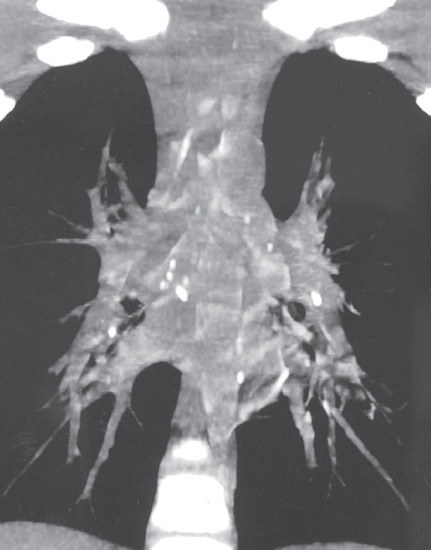

Поддерживающая терапия ОЛЛ проведена с 06.02.2013 по 19.08.2014 (назначены курсы метатрексата, дексаметазона), у ребенка констатирована стойкая ремиссия лейкоза. На фоне иммуносупрессивной терапии отмечались транзиторные изменения со стороны анализов крови (анемия, лейкопения, тромбоцитопения) от 12.03.2014: Er — 3,75 · 109/л, Hb — 105 г/л, Tr — 142 · 109/л, L — 2,9 · 109/л, п/я — 4 %, с/я — 41 %, мон. — 5 %, эоз. — 5 %, лимф. — 45 %, СОЭ — 16 мм/ч, с последующей нормализацией. В остальном состояние ребенка без патологических изменений. Курсы противотуберкулезной химиотерапии двумя препаратами (изониазид + пиразинамид и изониазид + ПАСК) проводили в периоды иммуносупрессивной терапии. Поддерживающая терапия ОЛЛ прекращена с 2015 г. Противорецидивное лечение туберкулеза продолжал в 2014 и 2015 гг. в летний период в санатории «Петродворец» (режим химиотерапии изониазид + пиразинамид). После 2016 г. курсов противотуберкулезной химиотерапии не получал, но контроль в противотуберкулезном диспансере был продолжен. Особенность контрольной иммунодиагностики туберкулеза состояла в следующем. В связи с медотводом гематолога с момента заболевания ОЛЛ в 2012–2014 гг. кожные иммунологические пробы не проводили. В 2013 и 2014 гг. проведен in vitro IGRA-тест — T-SPOT.TB, результат положительный. В 2015 г. проба Манту с 2 ТЕ: папула 17 мм, проба с аллергеном туберкулезным рекомбинантным — 20 мм. В связи с выраженной местной реакцией мать мальчика отказалась от дальнейшего проведения кожных проб. МСКТ органов грудной полости 2013, 2014, 2015 гг.: «Очаговых и инфильтративных изменений не выявлено. Изменения во всех группах внутригрудных лимфатических узлов стабильны, их размеры и степень кальцификации не нарастают». Последнее обследование в противотуберкулезном диспансере проведено в 2018 г. Ребенку было 12 лет, здоров. Туберкулезный контакт отсутствует (мать и тетя — клиническое излечение, дедушка переехал в другой регион). T-SPOT.TB — положительный. Обзорная рентгенограмма органов грудной полости — патологии не выявлено (рис. 4).

Рис. 4. Пациент, 12 лет. Обзорная рентгенограмма органов грудной клетки 16.08.2018 (6 лет наблюдения). Патологии не выявлено

Fig. 4. Patient, 12 years old. Plain X-ray of the chest organs 16.08.2018 (6 years of observation). No pathology was revealed

Клинический анализ крови — без патологии. Наблюдение в противотуберкулезном диспансере было завершено в 2018 г., в дальнейшем до настоящего времени наблюдается детской поликлиникой, здоров.